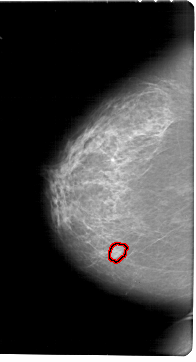

A_1789_1.RIGHT_MLO

RIGHT_MLO LINES 6871 PIXELS_PER_LINE 3886 BITS_PER_PIXEL 12 RESOLUTION 43.5 NON_OVERLAY

FILE: A_1789_1.LEFT_CC.OVERLAY

TOTAL_ABNORMALITIES 1

ABNORMALITY 1

LESION_TYPE MASS SHAPE LOBULATED MARGINS OBSCURED

ASSESSMENT 4

SUBTLETY 3

PATHOLOGY BENIGN

TOTAL_OUTLINES 1

BOUNDARY